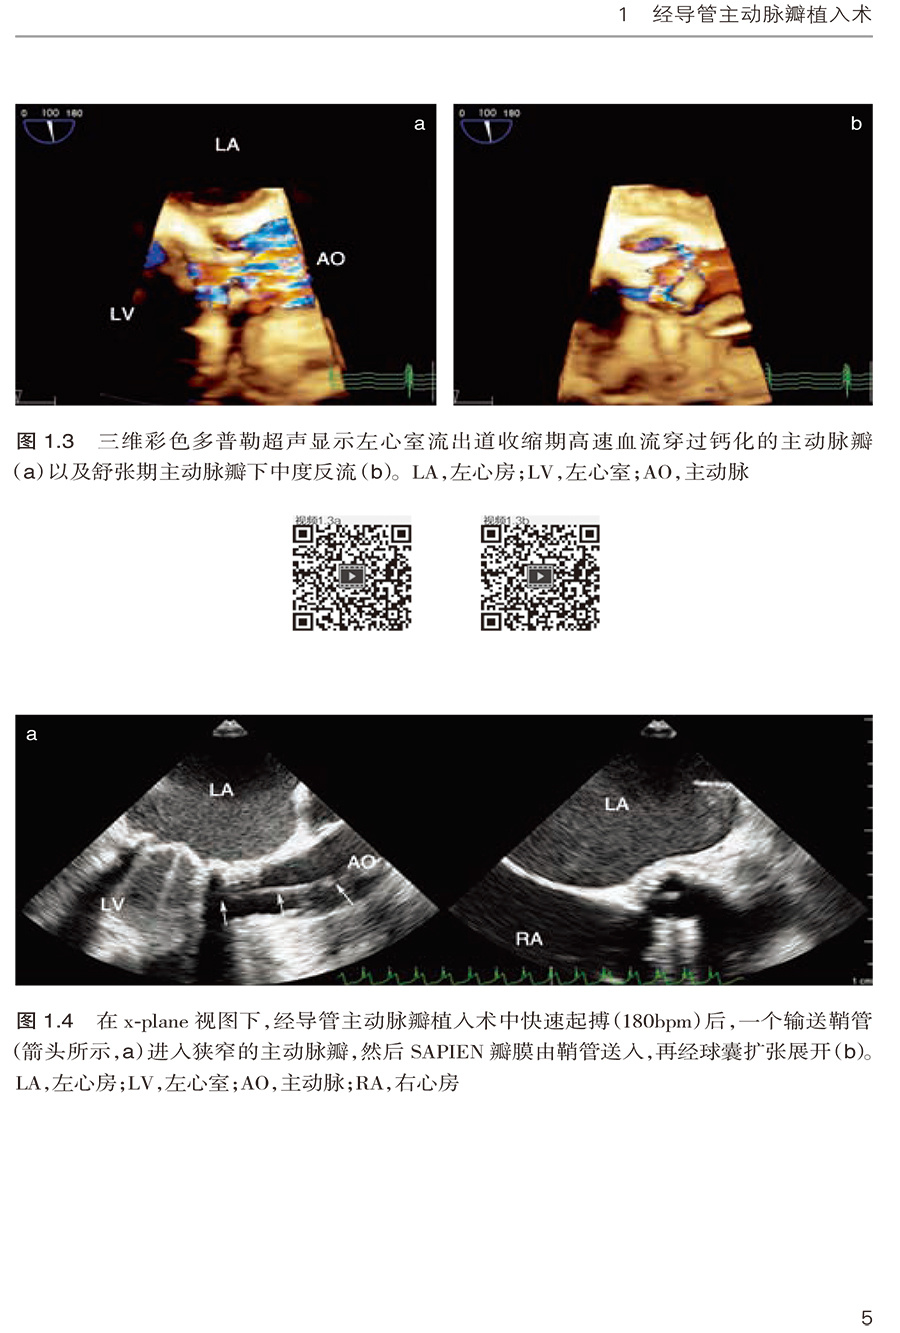

1.2 经心尖SAPIEN 瓣膜植入术 /3